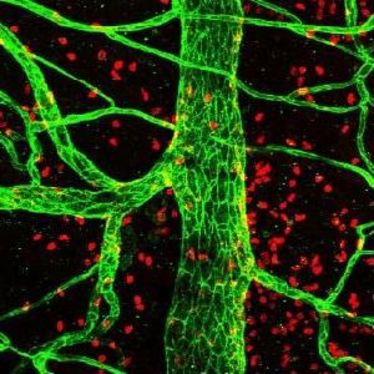

Biomolekülen auf der Spur

Biomolekülen auf der Spur